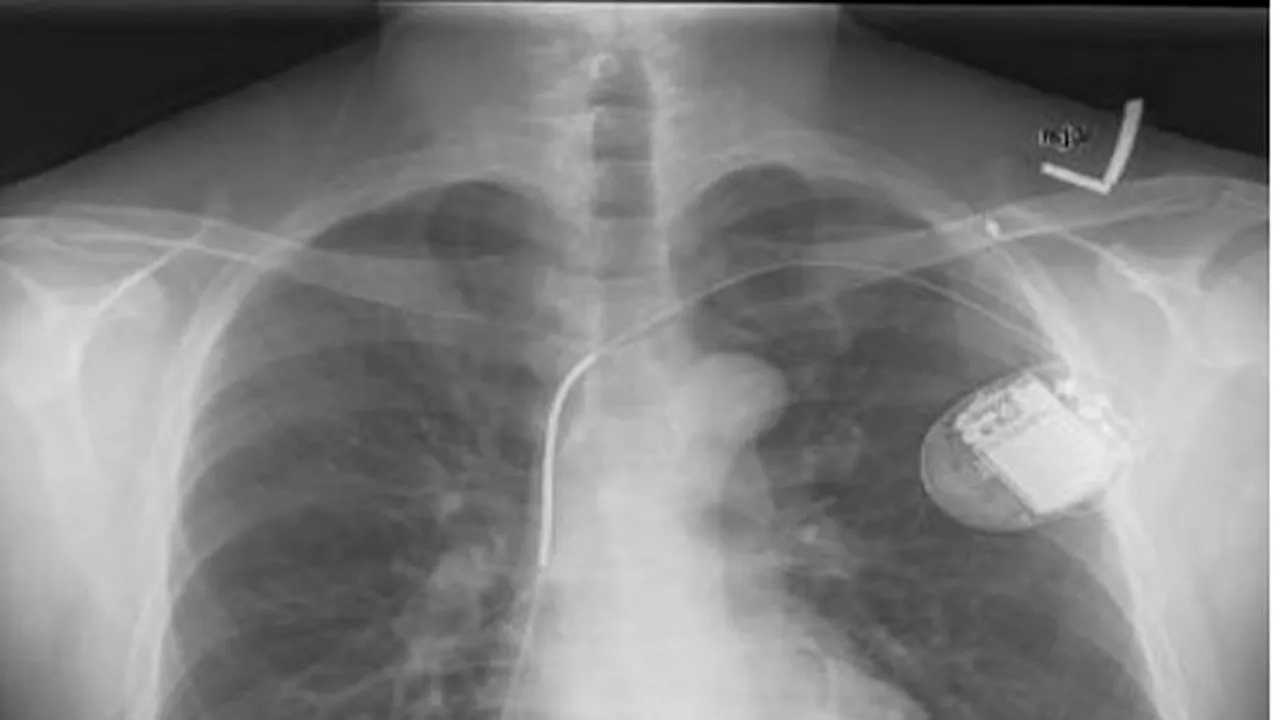

O echipă de cercetători, de la Universitatea Birmingham, din Marea Britanie, și Universitatea Leuven, din Belgia, a găsit potențiale erori medicale în zece implanturi diferite. Aceștia au descoperit vulnerabilități la nivelul sofware-ului și transmisiunii care asigură comunicarea cu stimulatorul cardiac implantat. Software-ul este utiizat pentru a updata aparatul și pentru a aduna date care radiografiază starea de sănătate e pacientului, potrivit BusinessInsider.

În demersul de remediere a erorilor, cercetătorii au reușit să opereze modificările necesare la nivelul dispozitivelor implantate și, în unele cazuri, chiar să le oprească funcționarea, dar și să obțină informații vitale despre pacient. Software-ul utilizat pentru astfel de aparate medicale precum stimulatorul cardiac îi ajută pe medici să monitorizeze evoluția pacientului și să se asigure că funcționează în parametri normali. Cu toate acestea, cercetătorii au putut să restarteze software-ul și regimul impulsurilor electrice transmise, alterând astfel comenzile.

„Am demonstrat, astfel, că resetarea comenzilor poate avea loc foarte facil, dacă persoana are acces la software și nu referim din punct de vedere fizic. Ipotetic, un atacator care ar avea echipamentul necesar la o distanță de cinci metri față de dispozitivul implantat ar putea să facă ce vrea”, arată cercetătorii.

De exemplu, un atacator ar putea să colecteze informații vitale cu privire la pacient și să schimbe comenzile dispozitivului, ceea ce poate fi fatal.

Pe de altă parte, cercetătorii au arătat că au putut să mențină stimulatorul pornit, deși au selectat opțiunea „standby mode”, ceea ce ar conduce la slăbirea mult mai rapidă a bateriei și la punerea sub risc a pacientului.